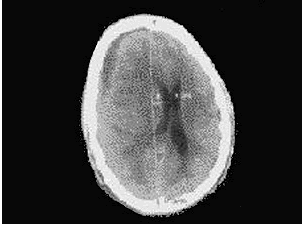

• 如图,为一右耳反复流脓20余年伴听力下降史的患者的头颅CT片,示有右额颞部硬膜下积脓,右颞部脑水肿,中线结构左移,脑底池变窄、欠清晰,两侧裂及脑沟不清,大脑镰下疝。有关耳源性脑脓肿描述正确的是()。

A.为脑组织内局限性积脓

B.多发生于小脑,其次为大脑颞叶

C.一般为单发,多发性者少见

D.致病菌以杆菌为主

E.也有混合感染者